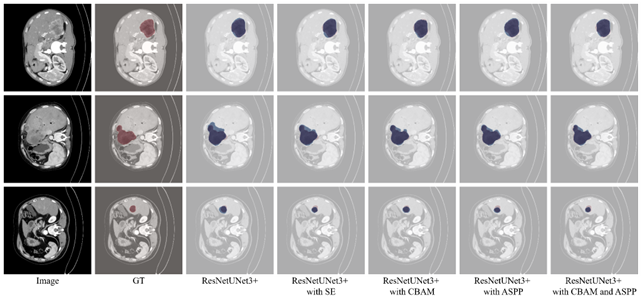

Refer to caption

Figure 9: The visual comparison of segmentation results of ResNetUNet3+ and its variants against ground truth on the testing set. The predicted and GT are highlighted in blue and red, respectively.

Figure 9 shows a qualitative comparison of segmentation results from the baseline model and its variants, including attention modules (SE, CBAM) and a multi-scale feature extractor (ASPP), against the ground truth on three test images. The baseline model generally identifies lesions well but sometimes produces imprecise boundaries. The CBAM variant offers improved segmentation accuracy, especially in capturing irregular lesion contours, as seen in the second row. This indicates that CBAM’s spatial and channel-wise attention enhances the model’s ability to differentiate lesions from healthy tissue, resulting in more precise masks.